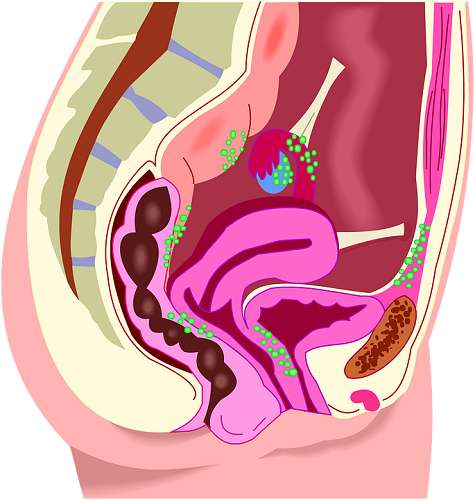

Женская репродуктивная система находится глубоко внутри организма, поэтому начинающиеся изменения в ней очень трудно заметить. Когда они становятся явными, иногда бывает уже поздно и требуется серьезное лечение, вплоть до удаления органов. К сожалению, рак шейки матки очень распространенное и смертельное заболевание, однако, если начать лечение на ранней стадии, его можно победить. Тревогу следует бить в следующих случаях.